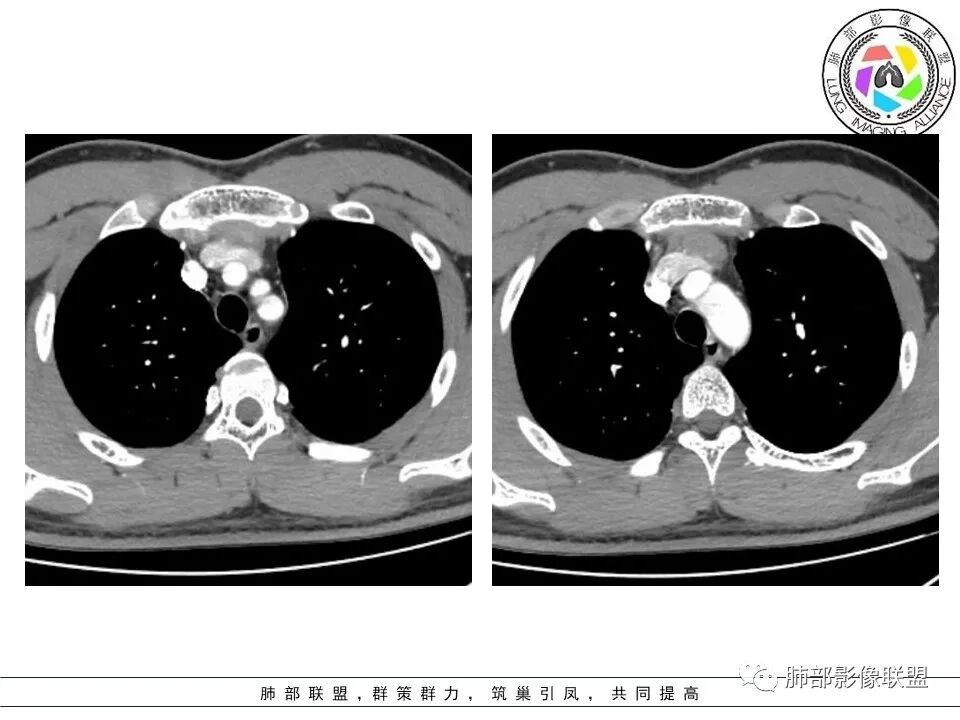

青少年无症状,前纵隔多个软组织结节,没有钙化,边界清,有强化,没有重症肌无力,考虑淋巴瘤,鉴别胸腺瘤,畸胎瘤,生殖细胞瘤,淋巴结增生,转移瘤

青少年,前纵膈软组织占位,密度均匀,边界欠清晰,增强病灶强化不明显,考虑淋巴瘤,鉴别胸腺增生,生殖细胞瘤

男,16岁,体检发现纵隔肿物,前纵隔多个软组织密度影,边界清晰,其内密度不均,增强扫描病灶轻度强化,考虑淋巴瘤可能,鉴别胸腺病变。

青少年男性,无症状,体检发现,前纵隔多个软组织结节影,边界尚清晰,密度不均,增强扫描轻度不均匀强化,考虑胸腺增生,鉴别:淋巴瘤(结节融合不明显,放第二吧),生殖细胞瘤(年轻人要考虑,需查AFP),纵隔结核(没肺窗,不知道肺上情况如何),其它如胸腺瘤,转移瘤等,一般发病年龄偏大,有原发肿瘤史,估计可能性不大。

青少年,前纵隔多个结节,密度不均,边界清晰,轻度不均匀强化,考虑胸腺增生,鉴别淋巴瘤,生殖细胞瘤。

周宇元-九江学院附属医院影像科: 青少年,体检发现前纵隔多发结节,轻度环形强化,考虑淋巴结结核,淋巴结炎?鉴别胸腺囊肿并感染,胸腺增生?